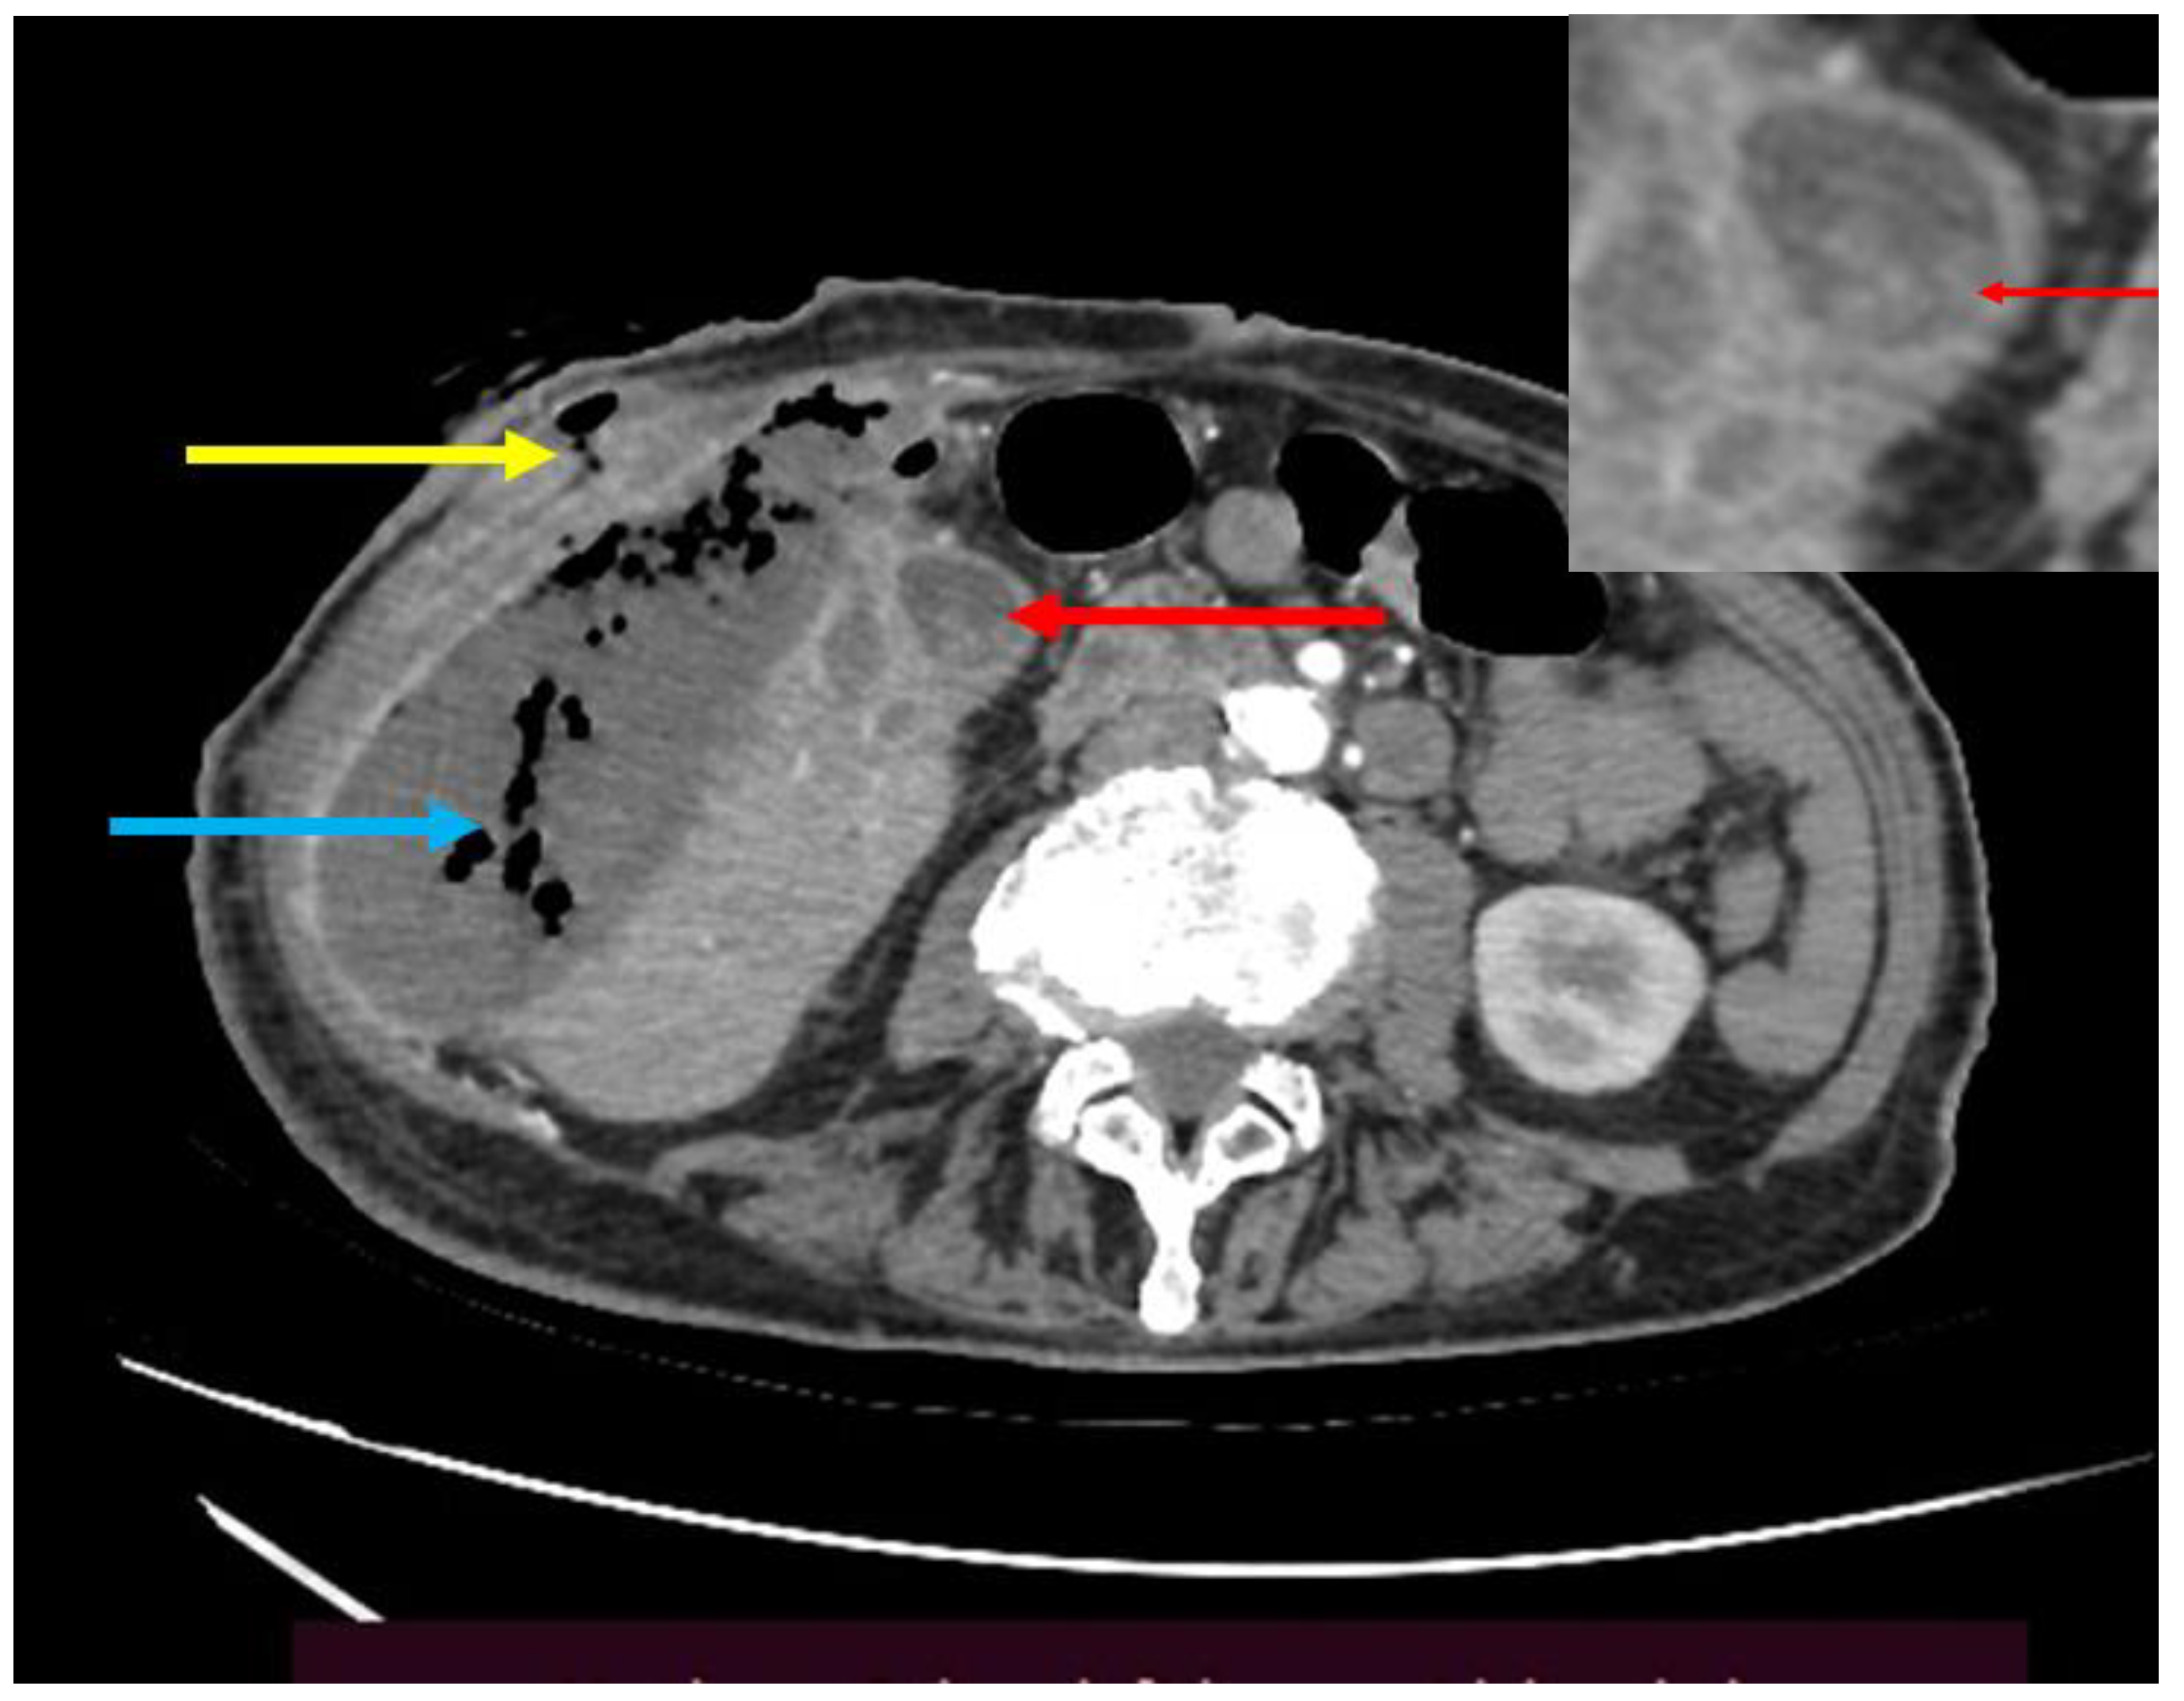

Computed tomography (CT) with IV and oral contrast offered further details (Figure 1). A voluminous (70x130 mm), parafluid collection with multiple gas bubbles located in the right flank; a fistulous tract exteriorized to the skin with several extensions infiltrating the muscular abdominal wall and the subcutaneous soft tissues. The collection communicated with multiple microabscesses in the GB fossa and also with a structure that resembled a GB with thick walls (in close vicinity to a normal duodenal stump), containing multiple opaque calculi (maxim 12 mm in diameter) and a gaseous image. Dilated intrahepatic bile ducts with pneumobilia were encountered. It was concluded that the abscess was secondary to a calculous cholecystitis and originated in the GB fossa.

Figure 1. Abdominal CT, transverse section. Fistulous tract (yellow arrow); right-flank suppurative gas-containing collection (blue arrow); gallbladder containing calculous material (red arrow).